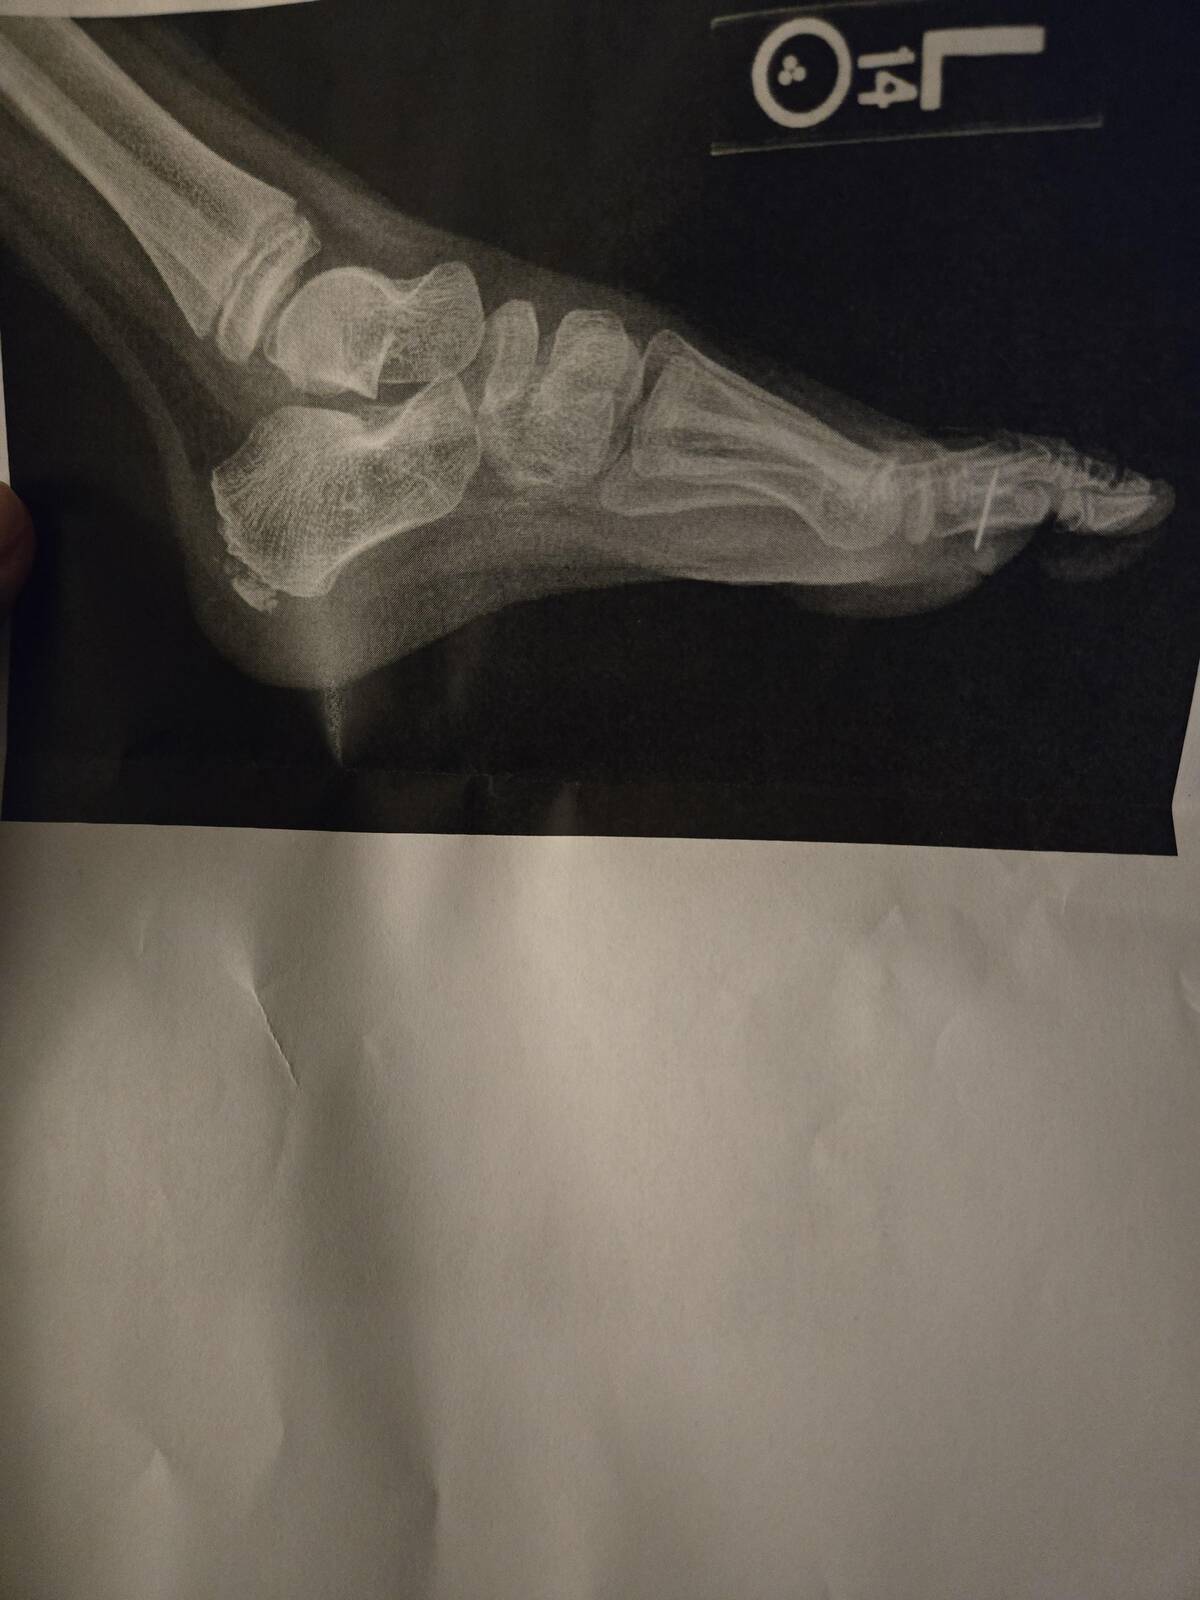

“My granddaughter stepped on a Hot wheel and had to have surgery to remove the axle.”

Hot Wheels: for when a simple ‘ouch’ just won’t do. Who knew a toy car could escalate into a surgical removal scenario? That’s one for the family stories (and maybe a cautionary tale for bare feet everywhere).